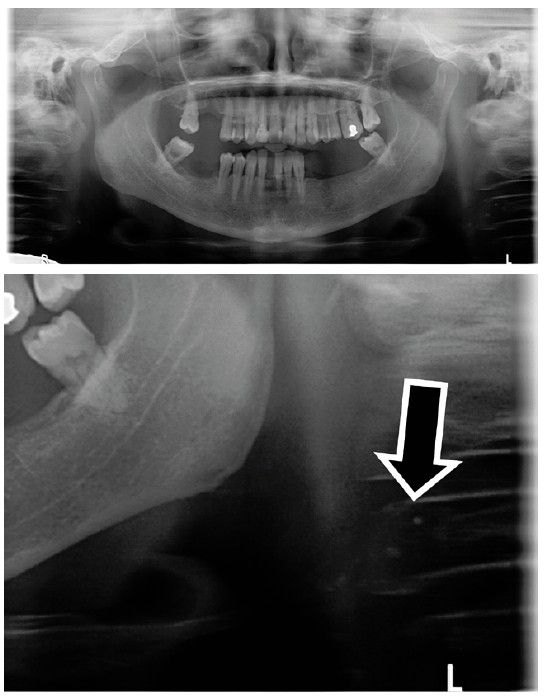

Estas calcificaciones que, generalmente se localizan en la bifurcación carotídea, se presentan como masas radiopacas en la región de la radiografía panorámica correspondiente a los tejidos blandos del cuello, en una zona aproximada entre las vértebras cervicales C2, C3 y C4, a una distancia aproximada entre 1 y 4 cm posteroinferior al ángulo mandibular13. Pueden variar en tamaño y forma, siendo lineales verticales, nodulares o heterogéneas, y pueden presentarse de manera unilateral o bilateral, así como ser únicas o múltiples13-15.

El objetivo de esta publicación es contribuir a la prevención de los problemas cerebrovasculares desde la clínica dental, mediante la presentación de tres casos clínicos en los que se detectaron de manera casual calcificaciones carotídeas durante un examen radiográfico de control, realizado mediante una radiografía panorámica, en pacientes con patologías periodontales en fase de mantenimiento.